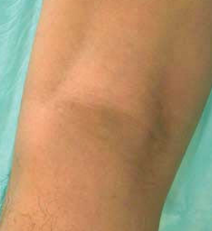

Bilateral Unexplained Upper-Thigh Bruises

Sweet F. Ver, MD; Henry Schneiderman, MD

<div id="article-content-body"><p><img src="/sites/default/files/old/img_4db9724f7a9af.jpg" style="margin-left: 8px; margin-right: 8px; float: left;"...